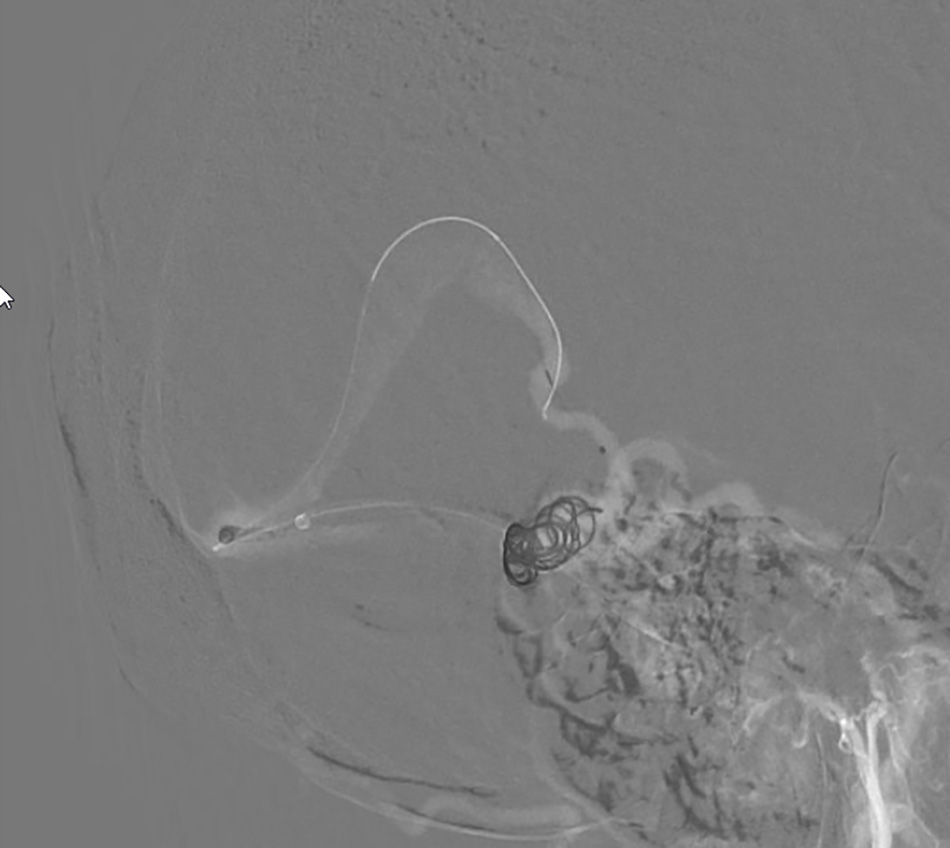

Interventional doctors thread the wire through the cerebral veins and begin deploying metal coils to occlude the aneurysm.

The image shows that the aneurysm has been completely occluded with coils.

Dr Huynh Huu Danh, Specialist Level I, performs an endovascular intervention to “patch” the patient’s ruptured brain aneurysm.

Through a small incision in the thigh, Dr Danh carefully guided a catheter and micro-guidewire through the vein to reach the aneurysm in the brain. A total of 12 coils (metallic spiral wires) were placed inside the aneurysm to “patch” the damaged area and block the blood flow through the rupture.